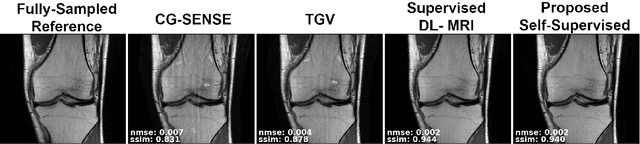

Abstract:Purpose: To develop a strategy for training a physics-driven MRI reconstruction neural network without a database of fully-sampled datasets. Theory and Methods: Self-supervised learning via data under-sampling (SSDU) for physics-based deep learning (DL) reconstruction partitions available measurements into two sets, one of which is used in the data consistency units in the unrolled network and the other is used to define the loss for training. The proposed training without fully-sampled data is compared to fully-supervised training with ground-truth data, as well as conventional compressed sensing and parallel imaging methods using the publicly available fastMRI knee database. The same physics-based neural network is used for both proposed SSDU and supervised training. The SSDU training is also applied to prospectively 2-fold accelerated high-resolution brain datasets at different acceleration rates, and compared to parallel imaging. Results: Results on five different knee sequences at acceleration rate of 4 shows that proposed self-supervised approach performs closely with supervised learning, while significantly outperforming conventional compressed sensing and parallel imaging, as characterized by quantitative metrics and a clinical reader study. The results on prospectively sub-sampled brain datasets, where supervised learning cannot be employed due to lack of ground-truth reference, show that the proposed self-supervised approach successfully perform reconstruction at high acceleration rates (4, 6 and 8). Image readings indicate improved visual reconstruction quality with the proposed approach compared to parallel imaging at acquisition acceleration. Conclusion: The proposed SSDU approach allows training of physics-based DL-MRI reconstruction without fully-sampled data, while achieving comparable results with supervised DL-MRI trained on fully-sampled data.

Abstract:Deep learning (DL) has emerged as a tool for improving accelerated MRI reconstruction. A common strategy among DL methods is the physics-based approach, where a regularized iterative algorithm alternating between data consistency and a regularizer is unrolled for a finite number of iterations. This unrolled network is then trained end-to-end in a supervised manner, using fully-sampled data as ground truth for the network output. However, in a number of scenarios, it is difficult to obtain fully-sampled datasets, due to physiological constraints such as organ motion or physical constraints such as signal decay. In this work, we tackle this issue and propose a self-supervised learning strategy that enables physics-based DL reconstruction without fully-sampled data. Our approach is to divide the acquired sub-sampled points for each scan into training and validation subsets. During training, data consistency is enforced over the training subset, while the validation subset is used to define the loss function. Results show that the proposed self-supervised learning method successfully reconstructs images without fully-sampled data, performing similarly to the supervised approach that is trained with fully-sampled references. This has implications for physics-based inverse problem approaches for other settings, where fully-sampled data is not available or possible to acquire.